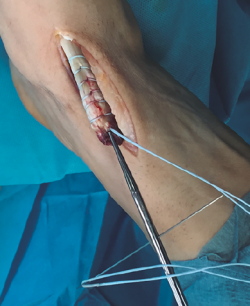

Figura 2. Tendón tibial anterior rescatado tras apertura del retinaculum superior.

Se prosigue con una disección de partes blandas, identificando y protegiendo las terminaciones nerviosas superficiales hasta llegar al retinaculum extensor, realizando apertura del mismo hasta encontrar el muñón proximal ascendido del TA (Figura 2). En los casos evolucionados o crónicos se puede apreciar una fibrosis que ocupa el compartimento del TA.

Figura 3. Sutura del tendón tibial anterior con hilo no absorbible.

Se realiza una disección y liberación del TA, resecando la porción distal más degenerada del tendón en forma de punta para introducirlo a través del túnel óseo con mayor facilidad y se sutura con hilo no absorbible (Figura 3), que después pasaremos a través de los orificios de la placa metálica de anclaje extracortical (de dimensiones de 4 × 12 mm).